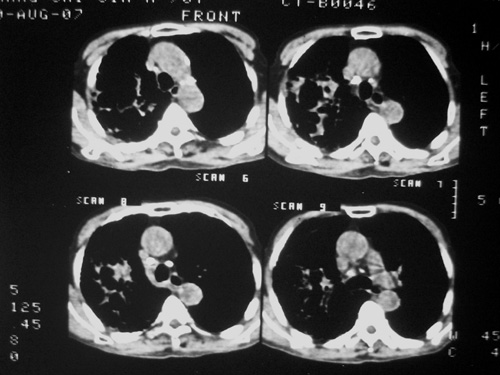

老年男性,70岁。煤矿工人20年。一周前咳嗽、发烧,拍x片考虑矽肺可能。始终咳嗽行ct检查,发现弥漫性病变,似感染但密度很高,细支气管肺泡癌无法排除,请老师给予指点。

矽肺,两肺间实质炎症,蜂窝肺。

矽肺  两肺间质性炎症伴纤维化(蜂窝肺)

矽肺合并右肺结核可能性大.右侧少量胸腔积液.